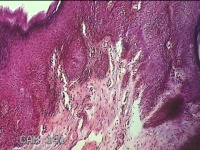

会阴部肿物

性别

男

年龄

47岁

临床诊断

1.皮肤肿物 2.尖锐湿疣?

一般病史

发现会阴部皮肤肿物2个月余。

标本名称

大体所见

灰白粉红色皮肤肿物0.8x0.5x0.3cm一个,表面光滑。

首先考虑湿疣。

良性病变。